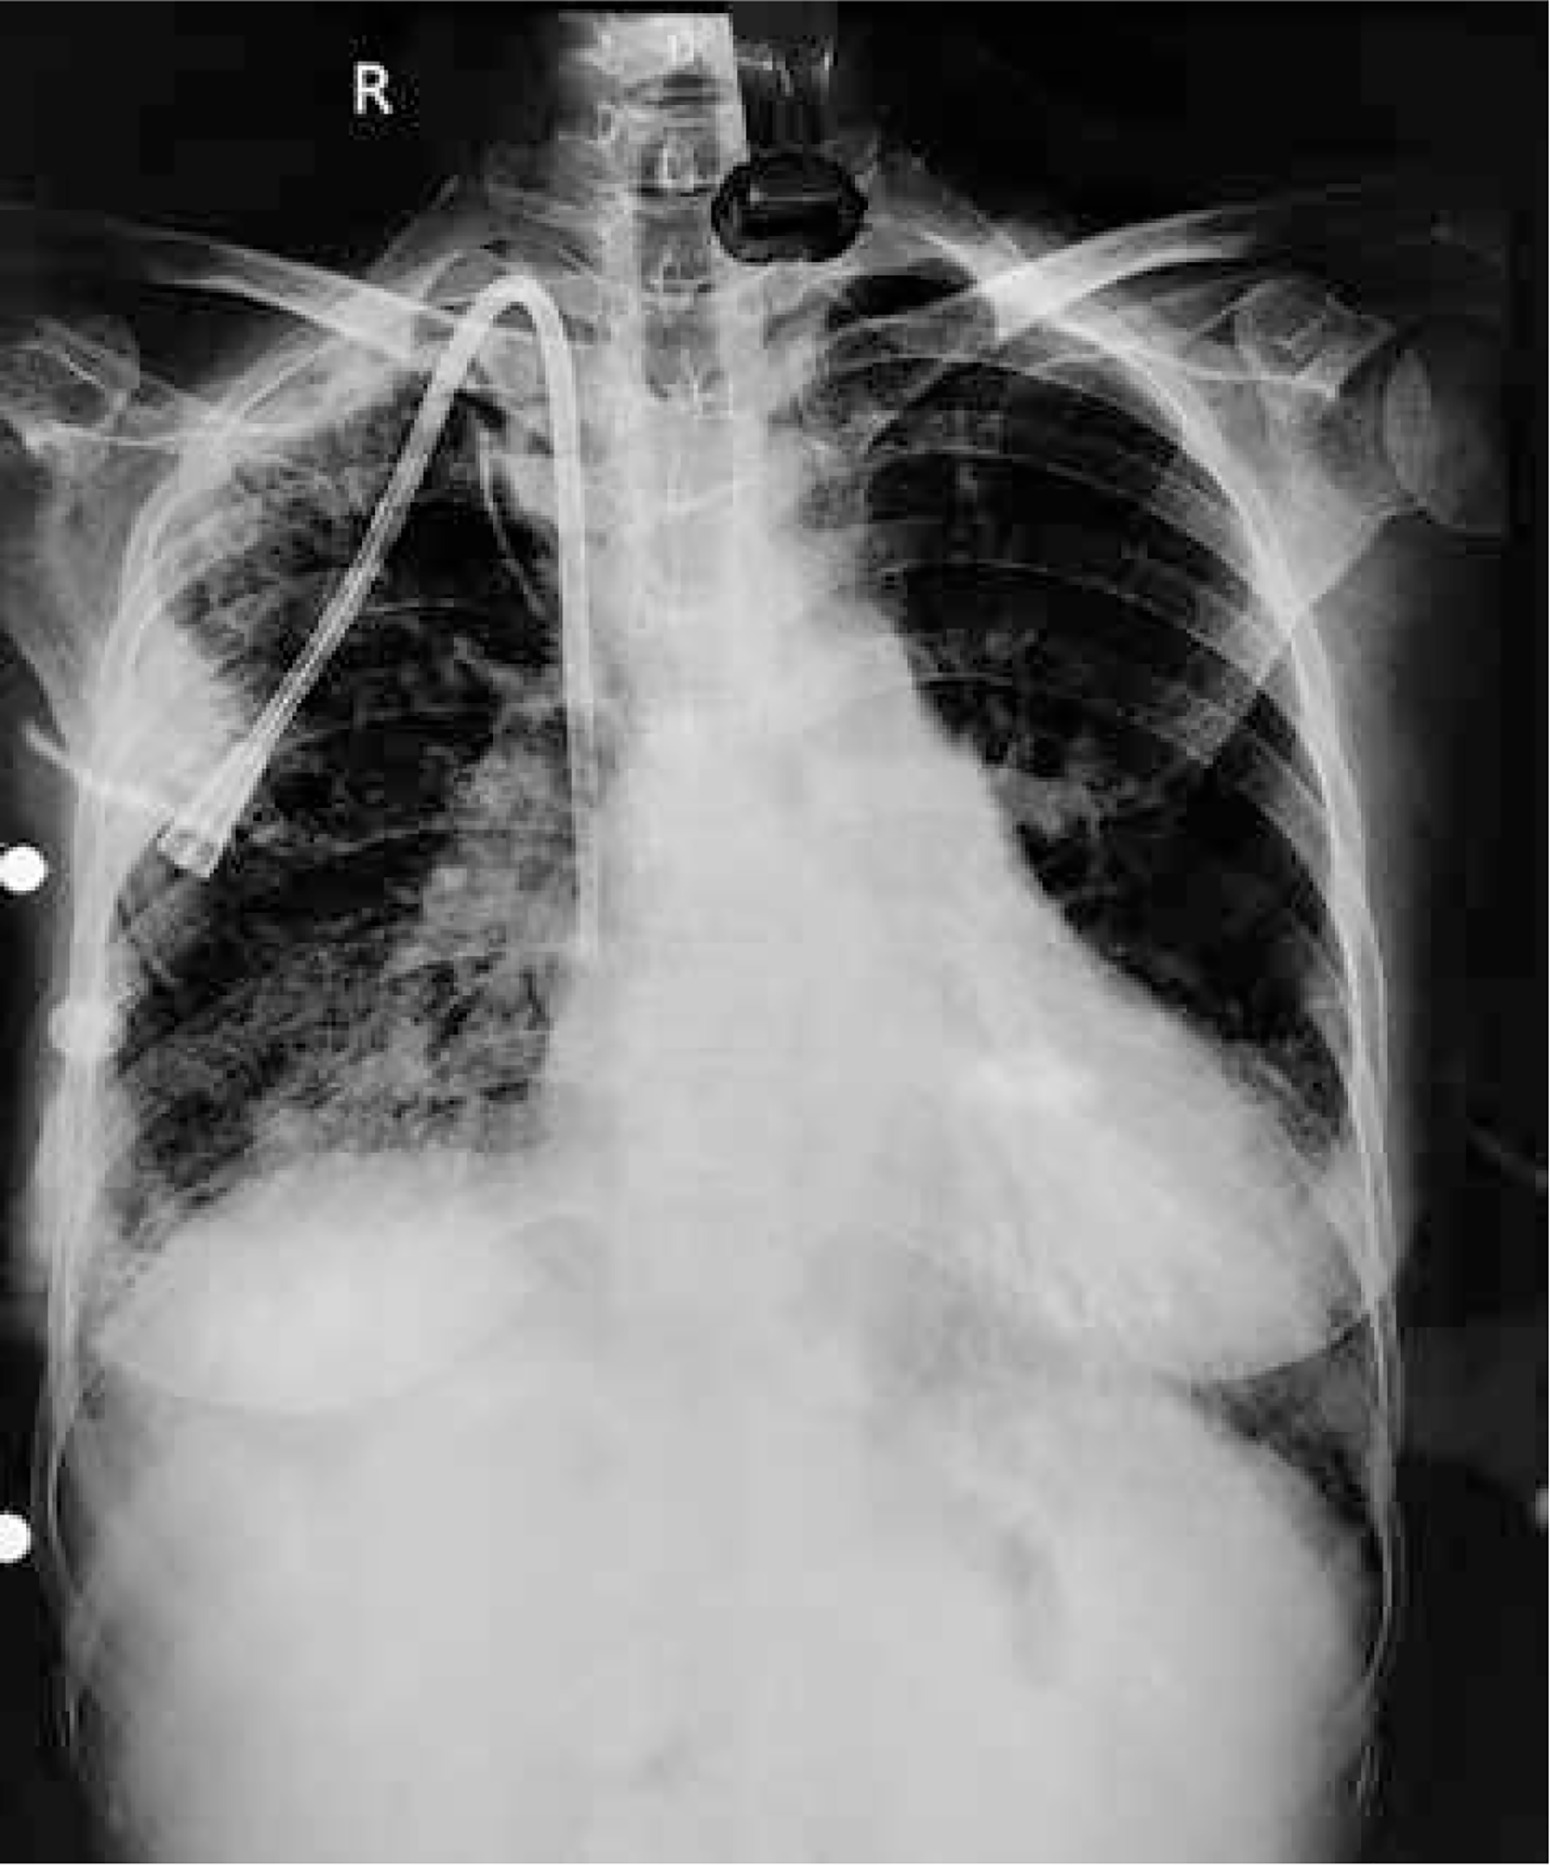

Invasive monitoring lines were taken. Standard midline sternotomy was done with preparations to go on cardiopulmonary bypass (CPB). Pericardiotomy revealed adhesions, hence the pericardium was initially opened minimally so as to allow purse string sutures over the aorta, superior vena cava and right atrium. The aorto-pulmonary septum and branches of the pulmonary artery were dissected. Cardiopulmonary bypass was instituted with aortocavoatrial cannulation as dissection around the pulmonary artery led to bleeding. The catheter tip was seen entering the roof of the left atrium after traversing through the right pulmonary artery (Figure 3). Purse string sutures were taken at the entry point of the catheter into the left atrium with polypropylene 4-0 (26 mm) and one of the two catheter tips was extracted from the LA. On tracing the catheter upwards, it was seen passing through the upper lobar branch of the right pulmonary artery avulsing and shearing it off at its origin and multiple places (Figure 4). The distal end of the avulsed artery was very friable and was in the midst of a group of matted lymph nodes. Due to these findings and given the compromised haemodynamics of the patient, we decided to sacrifice the upper lobar branch. After clamping the RPA, the catheter was extracted completely from the incision site and both ends of the avulsed branch of the RPA were under-run with polypropylene 5-0 (13 mm) sutures such that the RPA continued to supply the rest of the lung. Haemostasis was achieved and the patient was gradually weaned off bypass. The chest was closed over a mediastinal drain. Our total surgical time was 90 minutes with a CPB time of 40 minutes. After observing in the Cardiac ICU for 2 hours, the patient was shifted to the nephrology intensive care unit (ICU) on high ionotropic support of intravenous noradrenaline 0.2 μg/kg/min for further management. However, the patient had a stormy post-operative course complicated by respiratory failure and expired on the third post-operative day in the nephrology ICU. The exact cause of death could not be found as the relatives did not consent to a post mortem examination.

Figure 3

Catheter seen entering left atrial roof

SVC – superior vena cava, RAA – right atrial appendage.